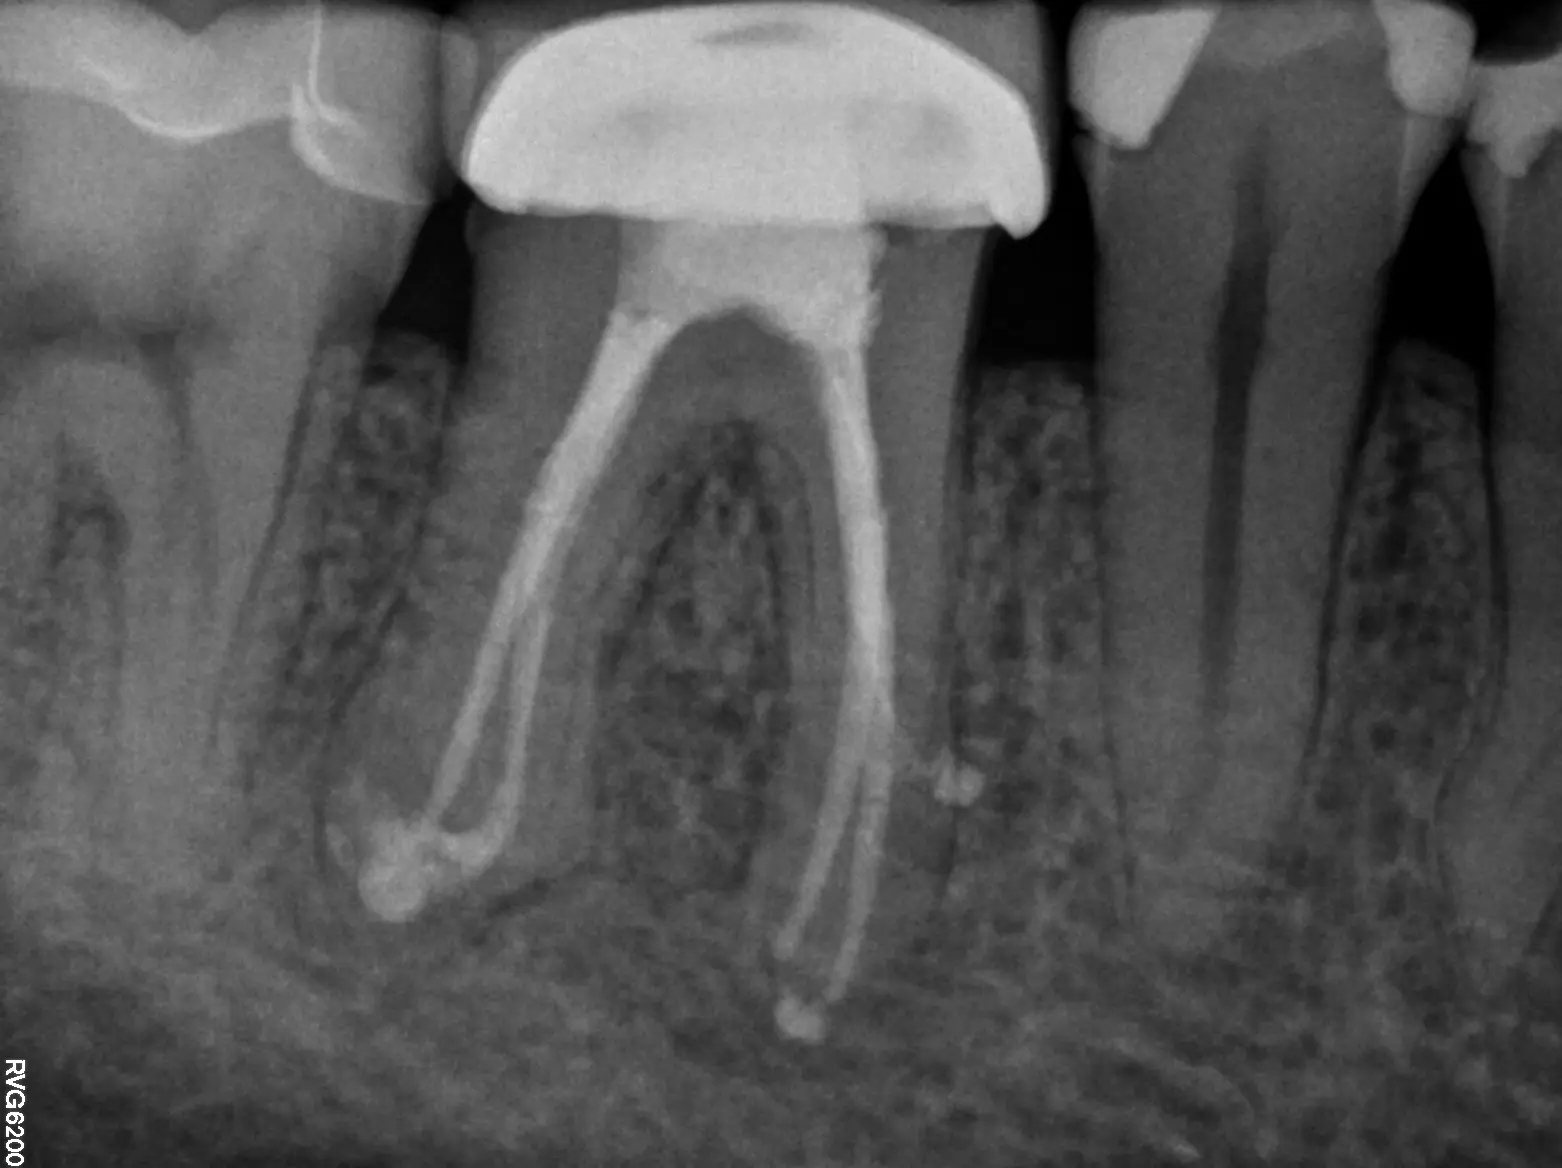

Filling & Sealing

Once your tooth has been completely cleaned and sanitized, the interior will be filled with a rubber-like material called gutta-percha. An inert material, gutta-percha replaces the extracted pulp and helps support the tooth and maintain its structure. Once the interior of the tooth has been filled, it will be restored with either a temporary or permanent filling to protect the tooth until a crown is placed by a general dentist if needed.

Your general dentist may have already taken some recent X-rays of your teeth before your visit with us. To arrive at a diagnosis and recommend treatment, we require specific angles of the tooth that can only be obtained with in-house imaging. We will do our best to obtain the images from your referring dentist and compare them to our own, so that we can review the complete picture with you